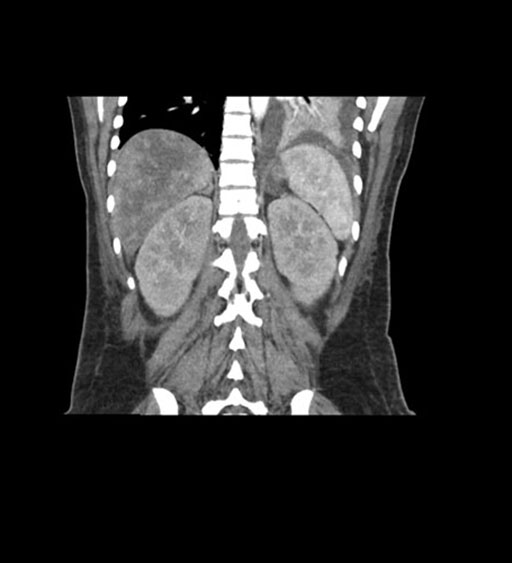

Imaging Analysis

Look through the patient's CT scan to identify any areas of concern for the necessary procedure.

Coronal Arterial